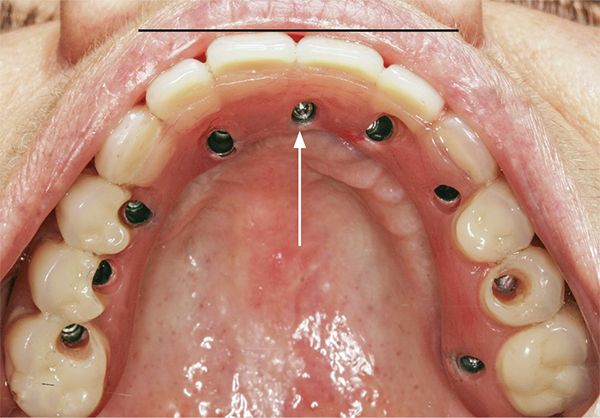

Fig 1. A periapical radiograph of an implant placed in the left central incisor position. The implant has an angulation toward the distal (arrows) to avoid penetration of the nasopalatine canal.

Figure 1

Several clinical approaches can be taken to replace a lost maxillary central incisor with a dental implant. An implant can be inserted to replace a tooth if there is sufficient bone height and width and the osteotomy can be created without encroaching on the nasopalatine canal. However, if the nasopalatine canal is close to the site of implant placement and it is desirable to avoid entering the canal, it may be possible to place the implant at an angle to avoid penetrating the canal (Figure 1). In this regard, if a misangulation of the implant is created intentionally, increased sink depth (distance from the implant platform to the gingival margin) will provide additional running room to facilitate creating a correct emergence profile for the restoration and tissue sculpting.